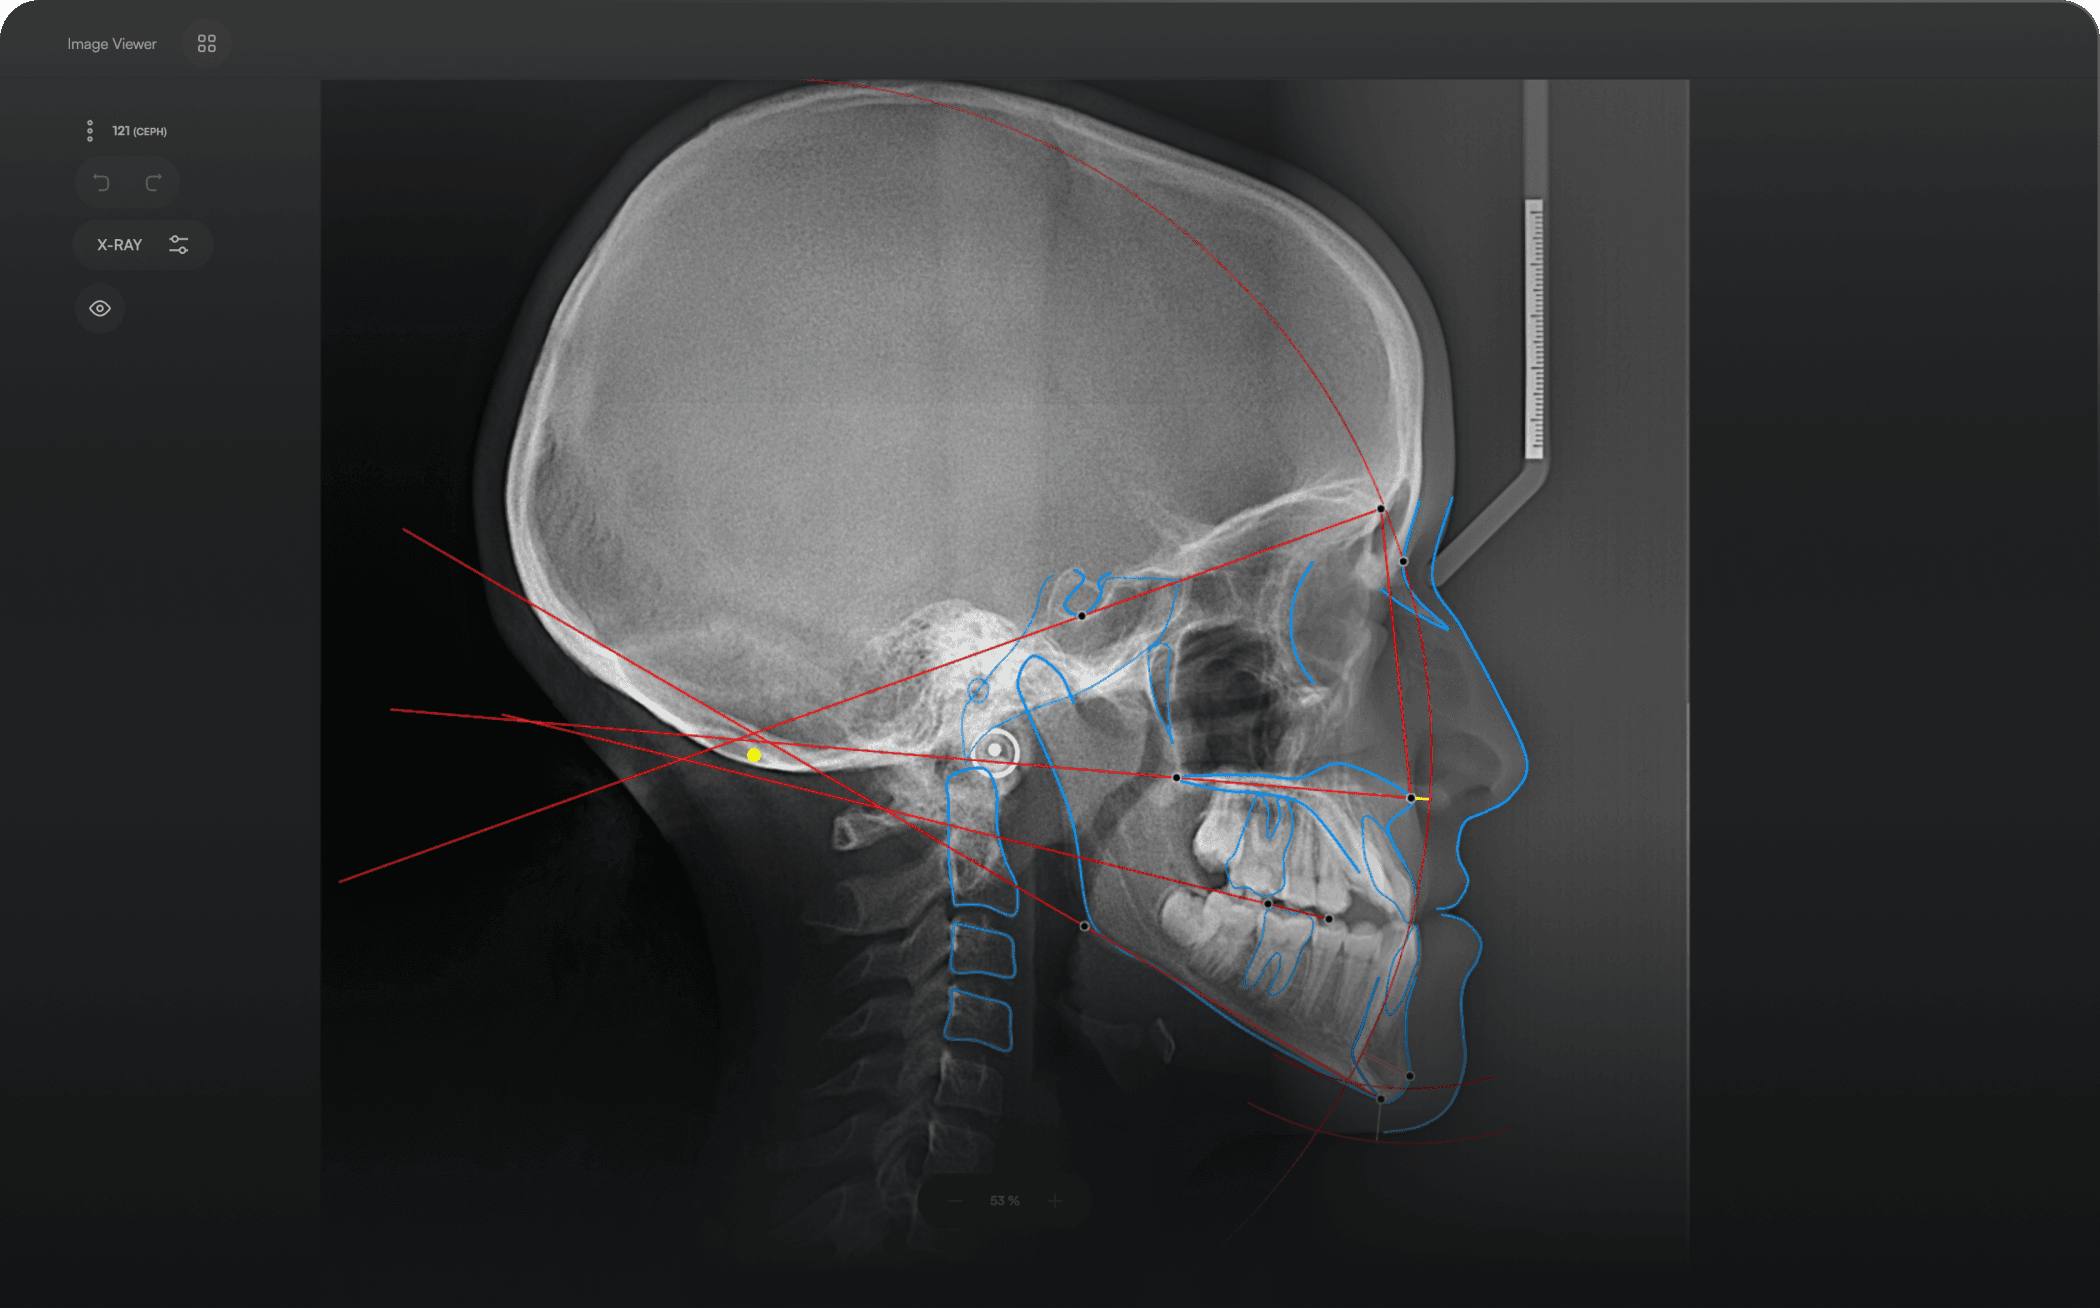

AI-driven Automated Lateral

Cephalometric Tracing

150+ landmarks traced in seconds

Automated analyses

Download detailed reports

Identify 150+ orthodontic landmarks in under 10 seconds — a task that

traditionally may take more than 30 minutes.